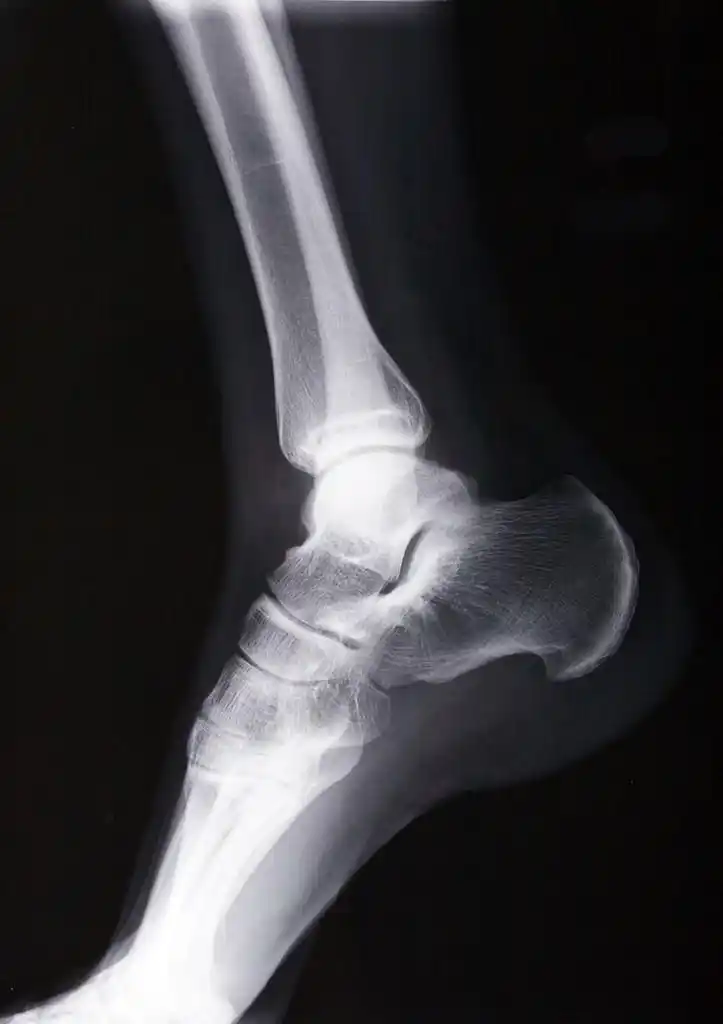

踝关节 x 线,男性人体踝关节 x 线图片

请骨科战友帮忙看一下左踝关节x线片 [病例帖]